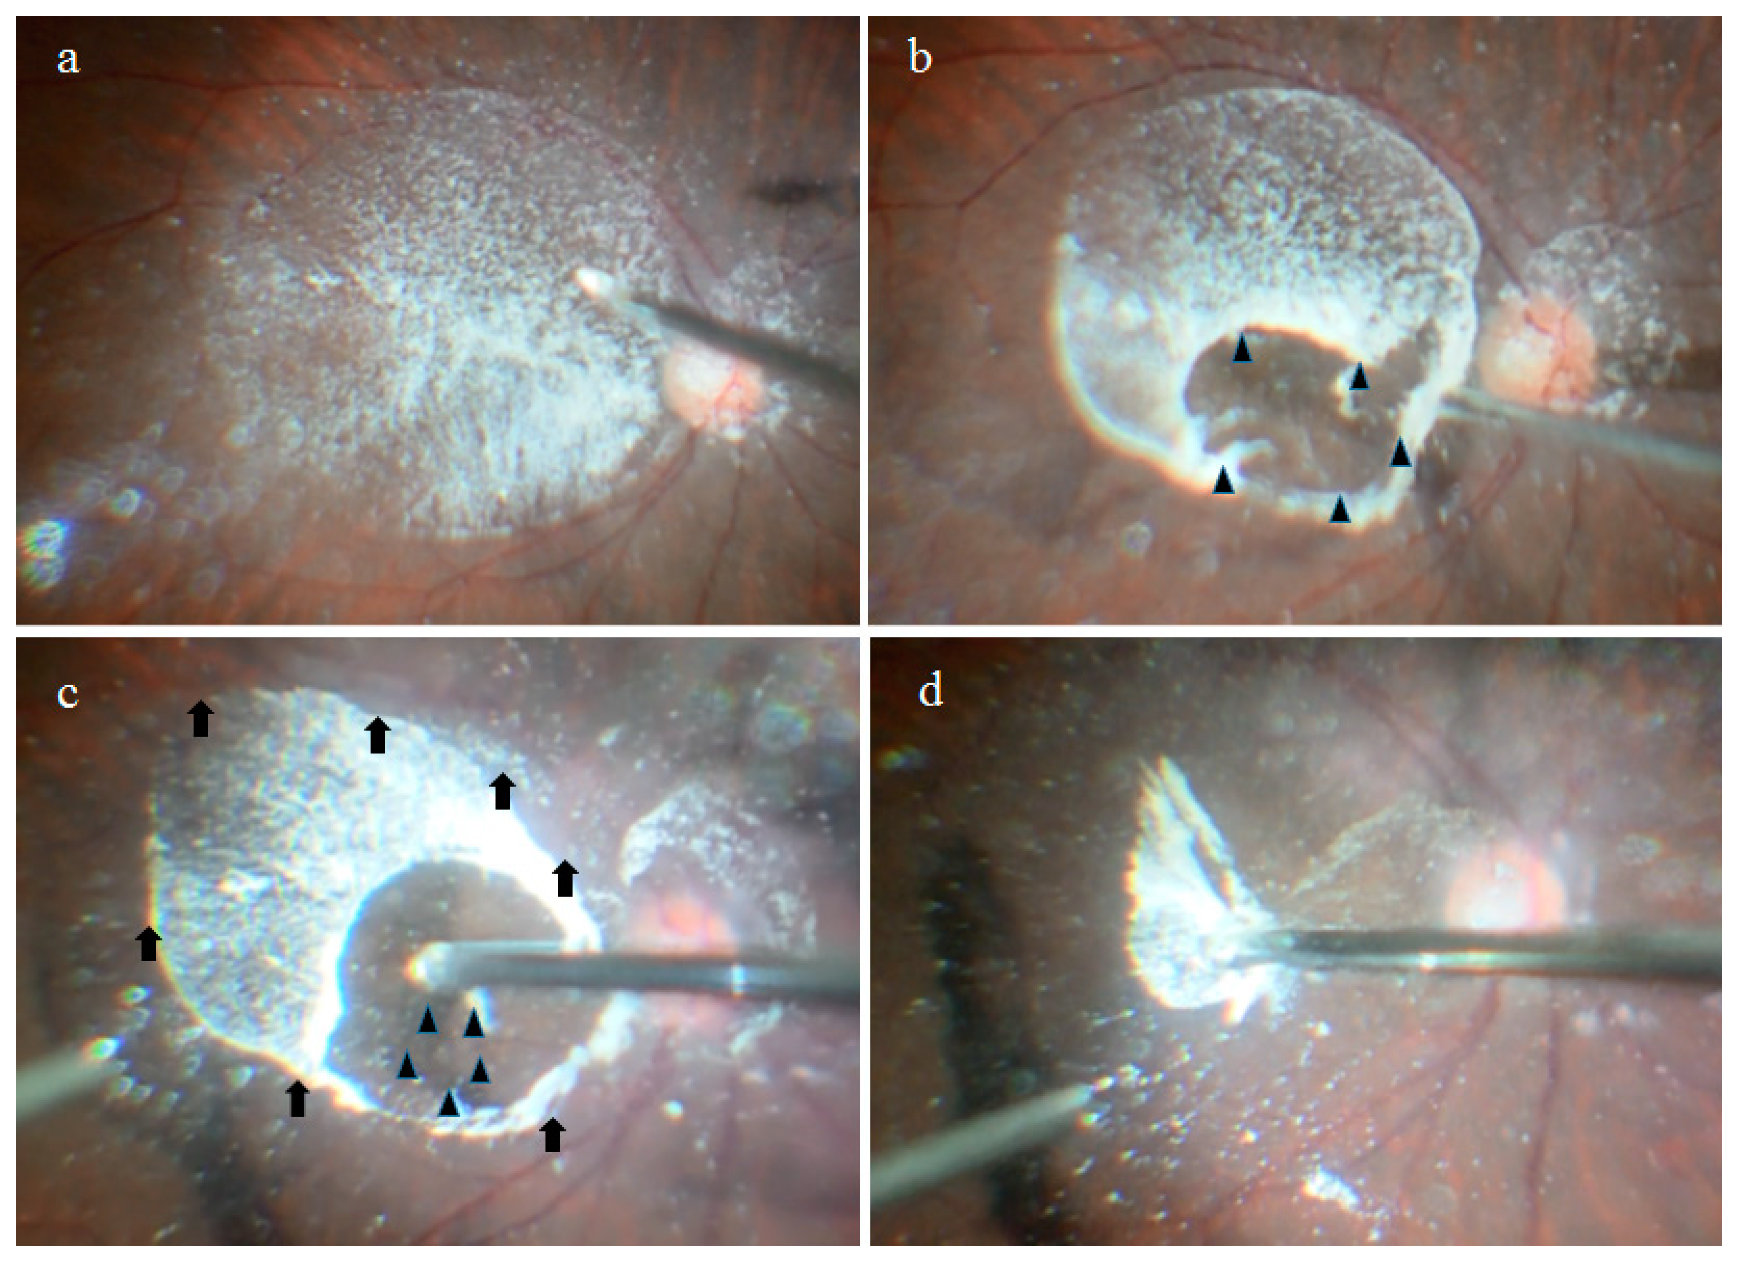

2.1. Anatomical Similarities between the BS and the BPM Observed during Specimen Collection

4.1. Collection of the BS, BPM, and VC Specimens